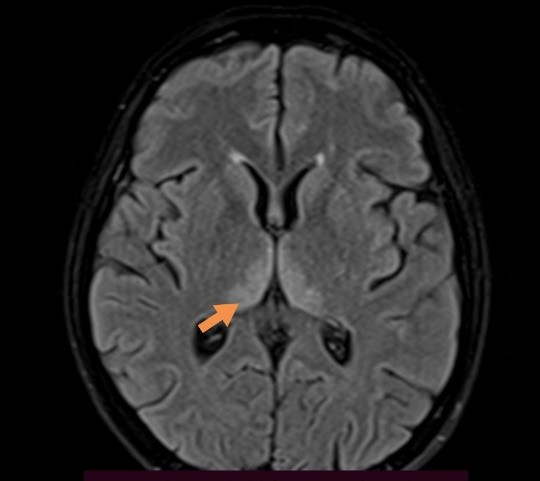

MRI of brain was obtained using postcontrast sequences with sagittal and axial T1, axial T2 and FLAIR and diffusion weighted imaging (DWI). On T2/FLAIR sequences there were hyperintensities in the medial part of both thalami and periaqueductal areas (Figure 1), which also showed DWI restriction – highly suggestive for of Wernicke´s encephalopathy (Figure 2).

| Figure 1. Presentation of hyperintensities in thalami and periaqueductal areas on MRI brain in T2/FLAIR sequence. | |